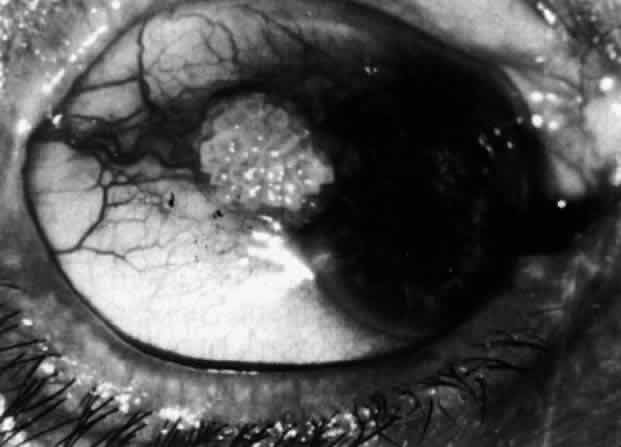

Necrotizing Anterior ScleritisdWithout Adjacent Inflammationd(Scleromalacia Perforans) Necrotizing anterior scleritis without adjacent inflammation appears to be a well-defined condition with little relation in clinical features to necrotizing scleral disease, even though the pathology is similar and the final result is the same. Scleromalacia perforans is characterized by the almost total lack of any symptoms. It occurs almost exclusively in patients with long-standing polyarticular rheumatoid arthritis, the majority of whom are female (Figs. 49 and 50; Color Plate 1E).

The anterior sclera loses its covering of episclera and develops an area of yellow-white necrotic slough over many months; this eventually separates or is absorbed, leaving the underlying choroid covered by either conjunctiva or nothing at all. As with necrotizing disease, the choroid does not bulge into this ectatic area; but unlike necrotizing disease, spontaneous healing of even small perforations is very limited once the necrotic tissue has been removed (see Fig. 50). Fluorescein angiography is not helpful, except to indicate areas of vascular closure in an otherwise extremely thin, atrophic episcleral tissue.4 The formation of a sequestrum appears to be caused by arteriolar closure as opposed to the venular disease seen in the other forms of necrotizing scleritis. Posterior Scleritis Because the posterior sclera is invisible, the diagnosis of posterior scleritis is made only if the anterior sclera is also involved or some other sign or symptom leads one to suspect it. Posterior scleritis is much more common than previously suspected, as recent clinical and pathologic studies have shown.19,28,29 There are two distinct forms of posterior scleritis. The first is usually associated with an anterior scleritis. This granulomatous disorder, like its anterior counterpart, can be diffuse, nodular, or necrotizing in character and is associated with the connective tissue diseases. The second form occurs in young patients of all races who are 9 to 40 years of age. It is always diffuse in character but is not associated with any systemic disorder. Both forms may cause uveitis if the inflammation affects the ciliary body, and in both forms the patient may develop exudative retinal detachments, choroidal folds, and swelling of the disc (Figs. 51 and 52). The granulomatous type may also involve the structures outside the globe, causing proptosis (Fig. 53), limitation of ocular muscle movement, and, uniquely, retraction of the lower lid on attempted elevation of the eye (Fig. 54). Diagnosis is with B-scan ultrasonography. TREATMENT Scleritis is almost always accompanied by very severe pain that prevents sleep. A response to treatment is heralded by a dramatic relief of pain even though the condition might appear to be getting worse (Figs. 55 through 59). Treatment may be modified with confidence once the pain has disappeared.